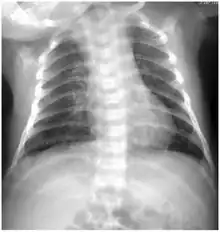

Chest X-ray - Diffuse patchiness on chest radiography in a neonate with Chlamydia trachomatis.

As many as half of all infants born to mothers with chlamydia will be born with the disease. Chlamydia can affect infants by causing spontaneous abortion; premature birth; conjunctivitis, which may lead to blindness; and pneumonia.[24] Conjunctivitis due to chlamydia typically occurs one week after birth (compared with chemical causes (within hours) or gonorrhea (2–5 days)).